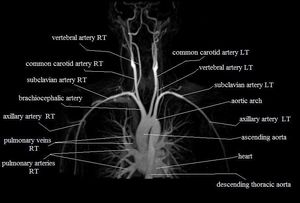

Magnetic Resonance Angiography (MRA) of the Chest!

Mri

Mra

Mr Anatomy